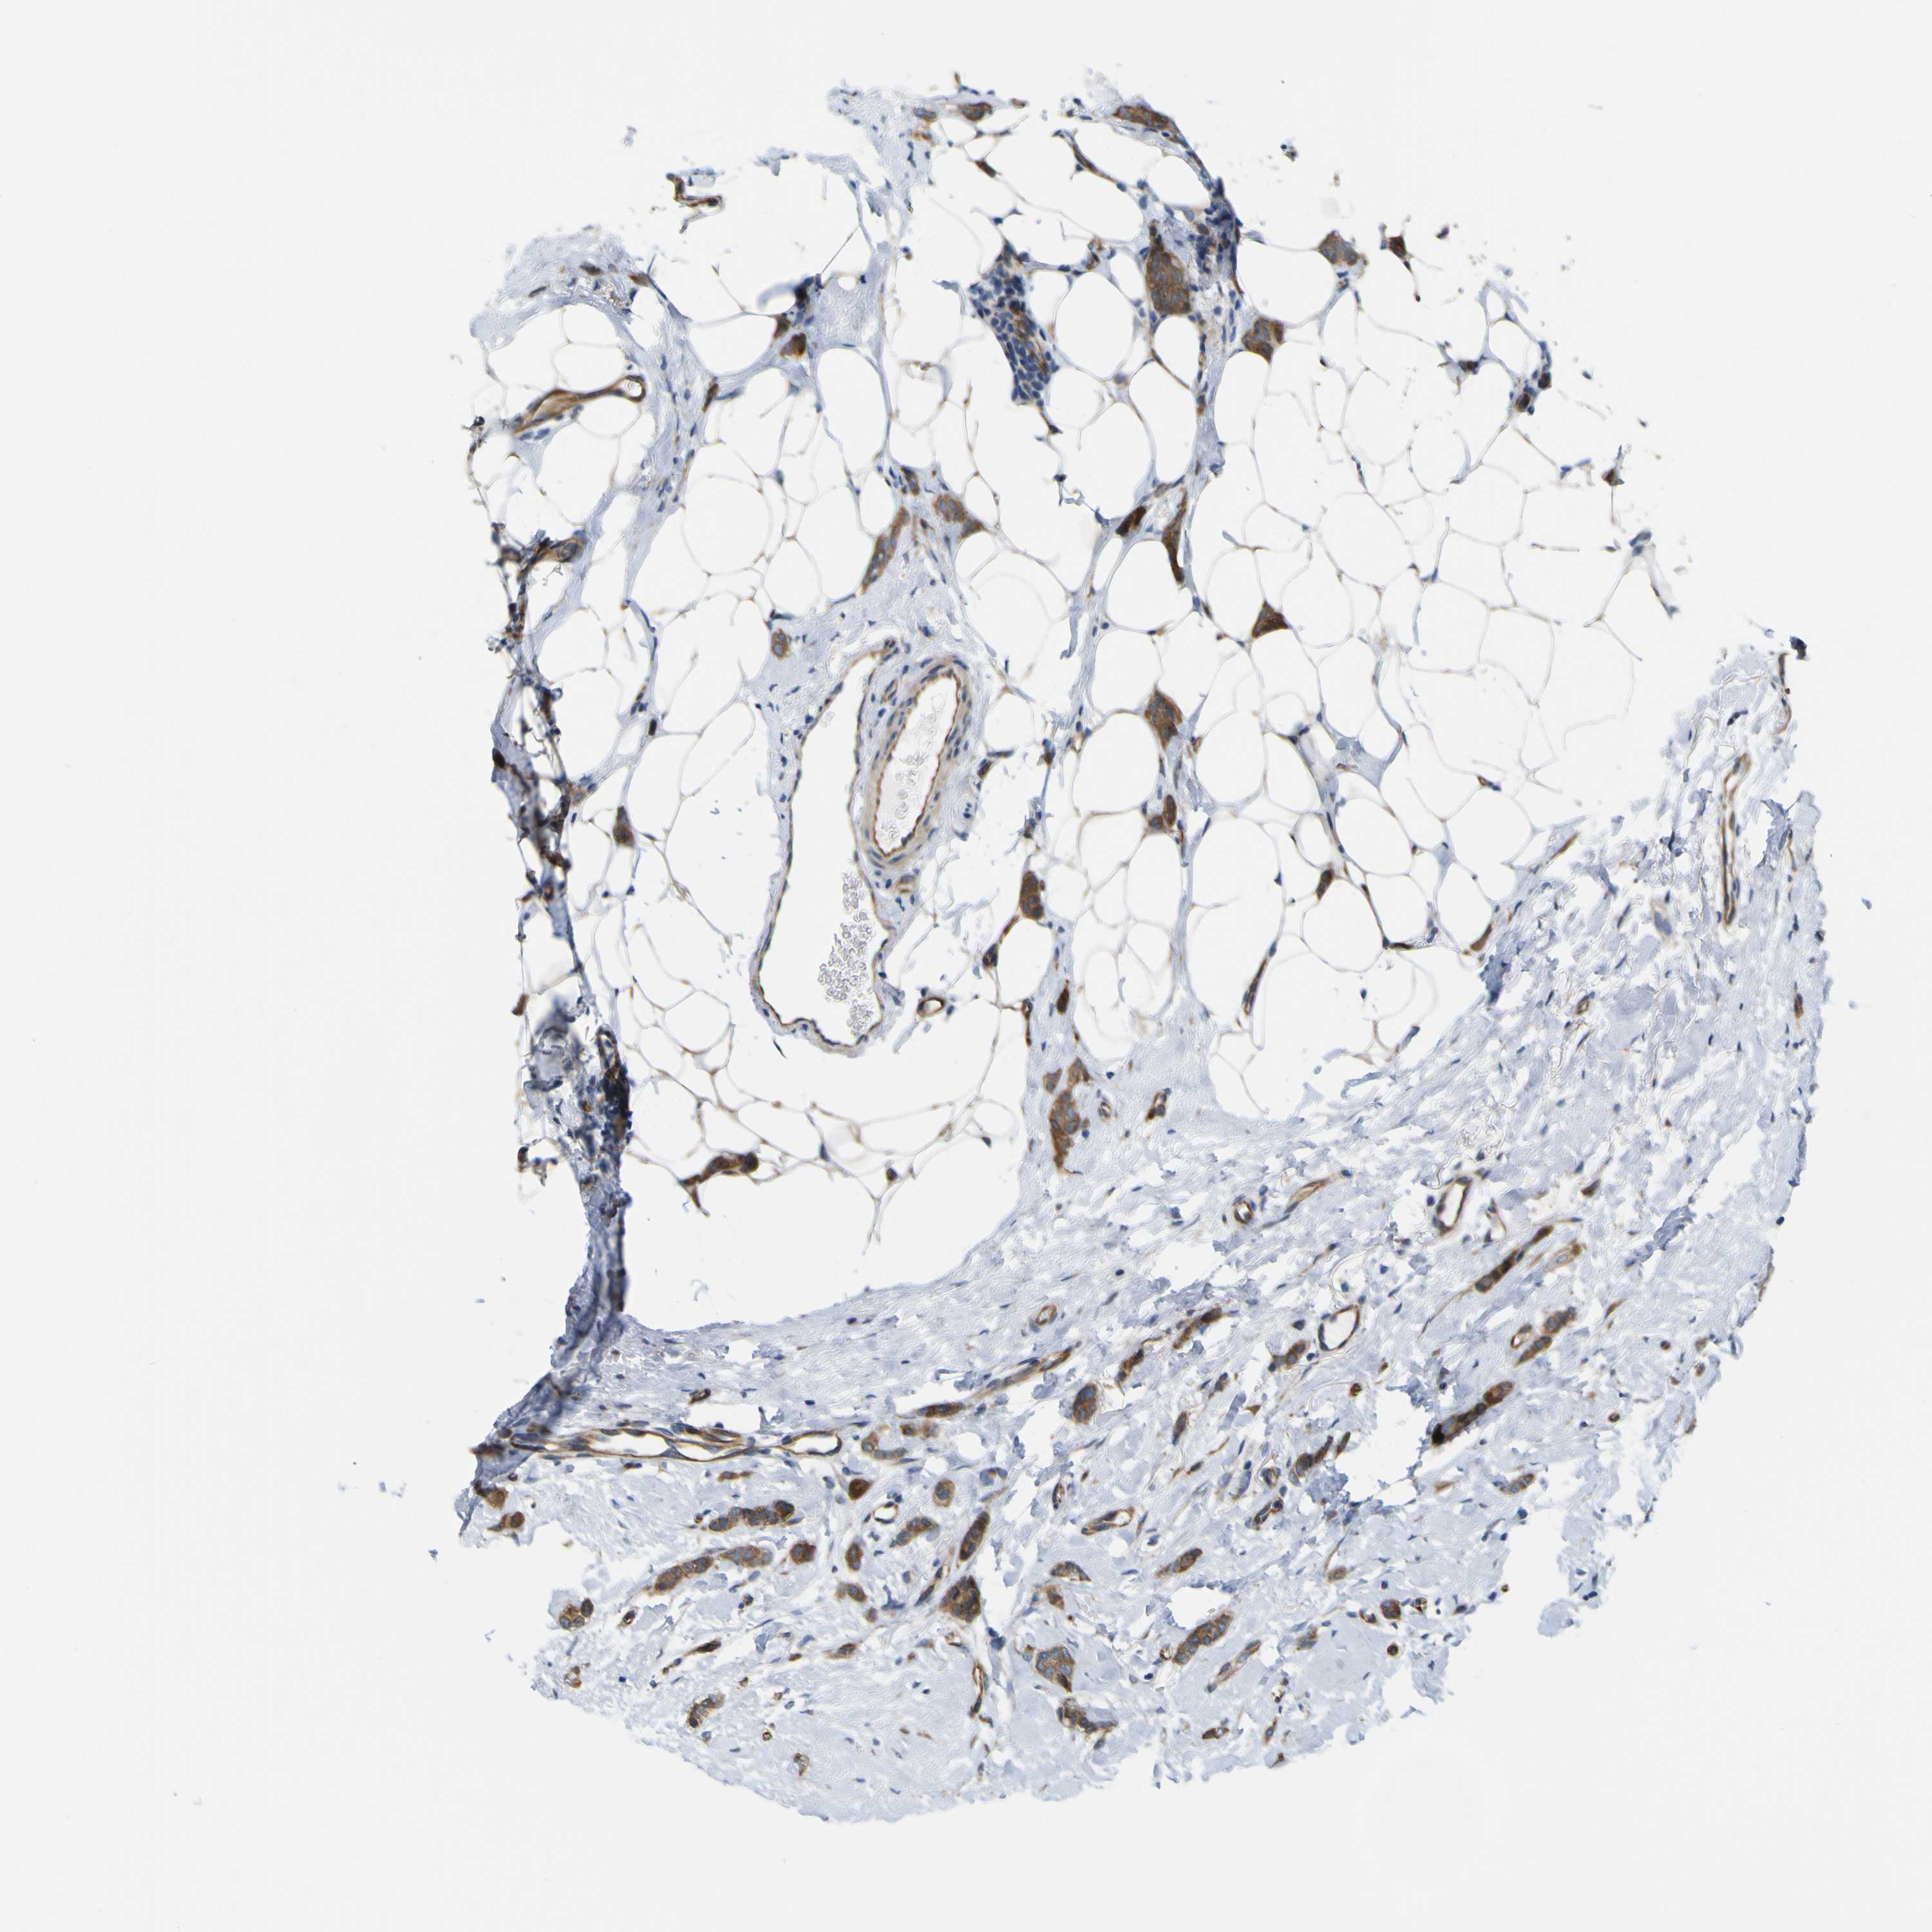

CANCER BREAST CANCER Show tissue menu

BRCA TCGA BRCA VALIDATION PROTEIN EXPRESSION